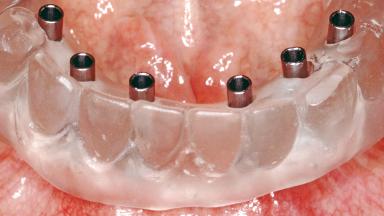

Conventional Loading of Six Implants in the Mandible and Final Restoration with a Full-Arch Metal-Ceramic FDP

# of Implants 6

Prosthesis Type FDP

Loading Protocol Conventional/early

Retention Screw-retained, with 4 or more splinted implants Screw-retained, with 4 or more splinted implants

Inter-Arch Distance Adequate